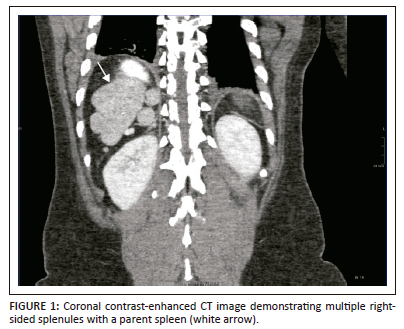

A CT of the abdomen revealed right-sided polysplenia (Figure 1) with a dominant parent spleen, a left-sided liver, extending across the midline, and a right-sided stomach (Figure 2). The superior mesenteric artery and vein were parallel to one another (Figure 3). The duodenum coursed anterior to the portosplenic vein with the duodenojejunal junction located to the left of the left-sided vertebral body pedicle but inferior to the level of the duodenal bulb, in keeping with some degree of malrotation. The jejunal loops were located in the left side of the abdomen. There was twisting of the mesentery in the right lower quadrant (Figure 4) with small bowel dilatation and massive dilatation of the caecum and proximal ascending colon (Figure 5). The transition point was within the proximal to mid ascending colon, with collapse of the large bowel distal to this point. There was also dilatation of the small bowel, most likely due to an incompetent ileocecal valve. A small amount of free fluid was noted in the right paracolic gutter and the Pouch of Douglas with multiple mesenteric lymph nodes in the right iliac fossa. Additionally, there was absence of the uncinate process of the pancreas suggestive of a truncated pancreas (Figure 3).